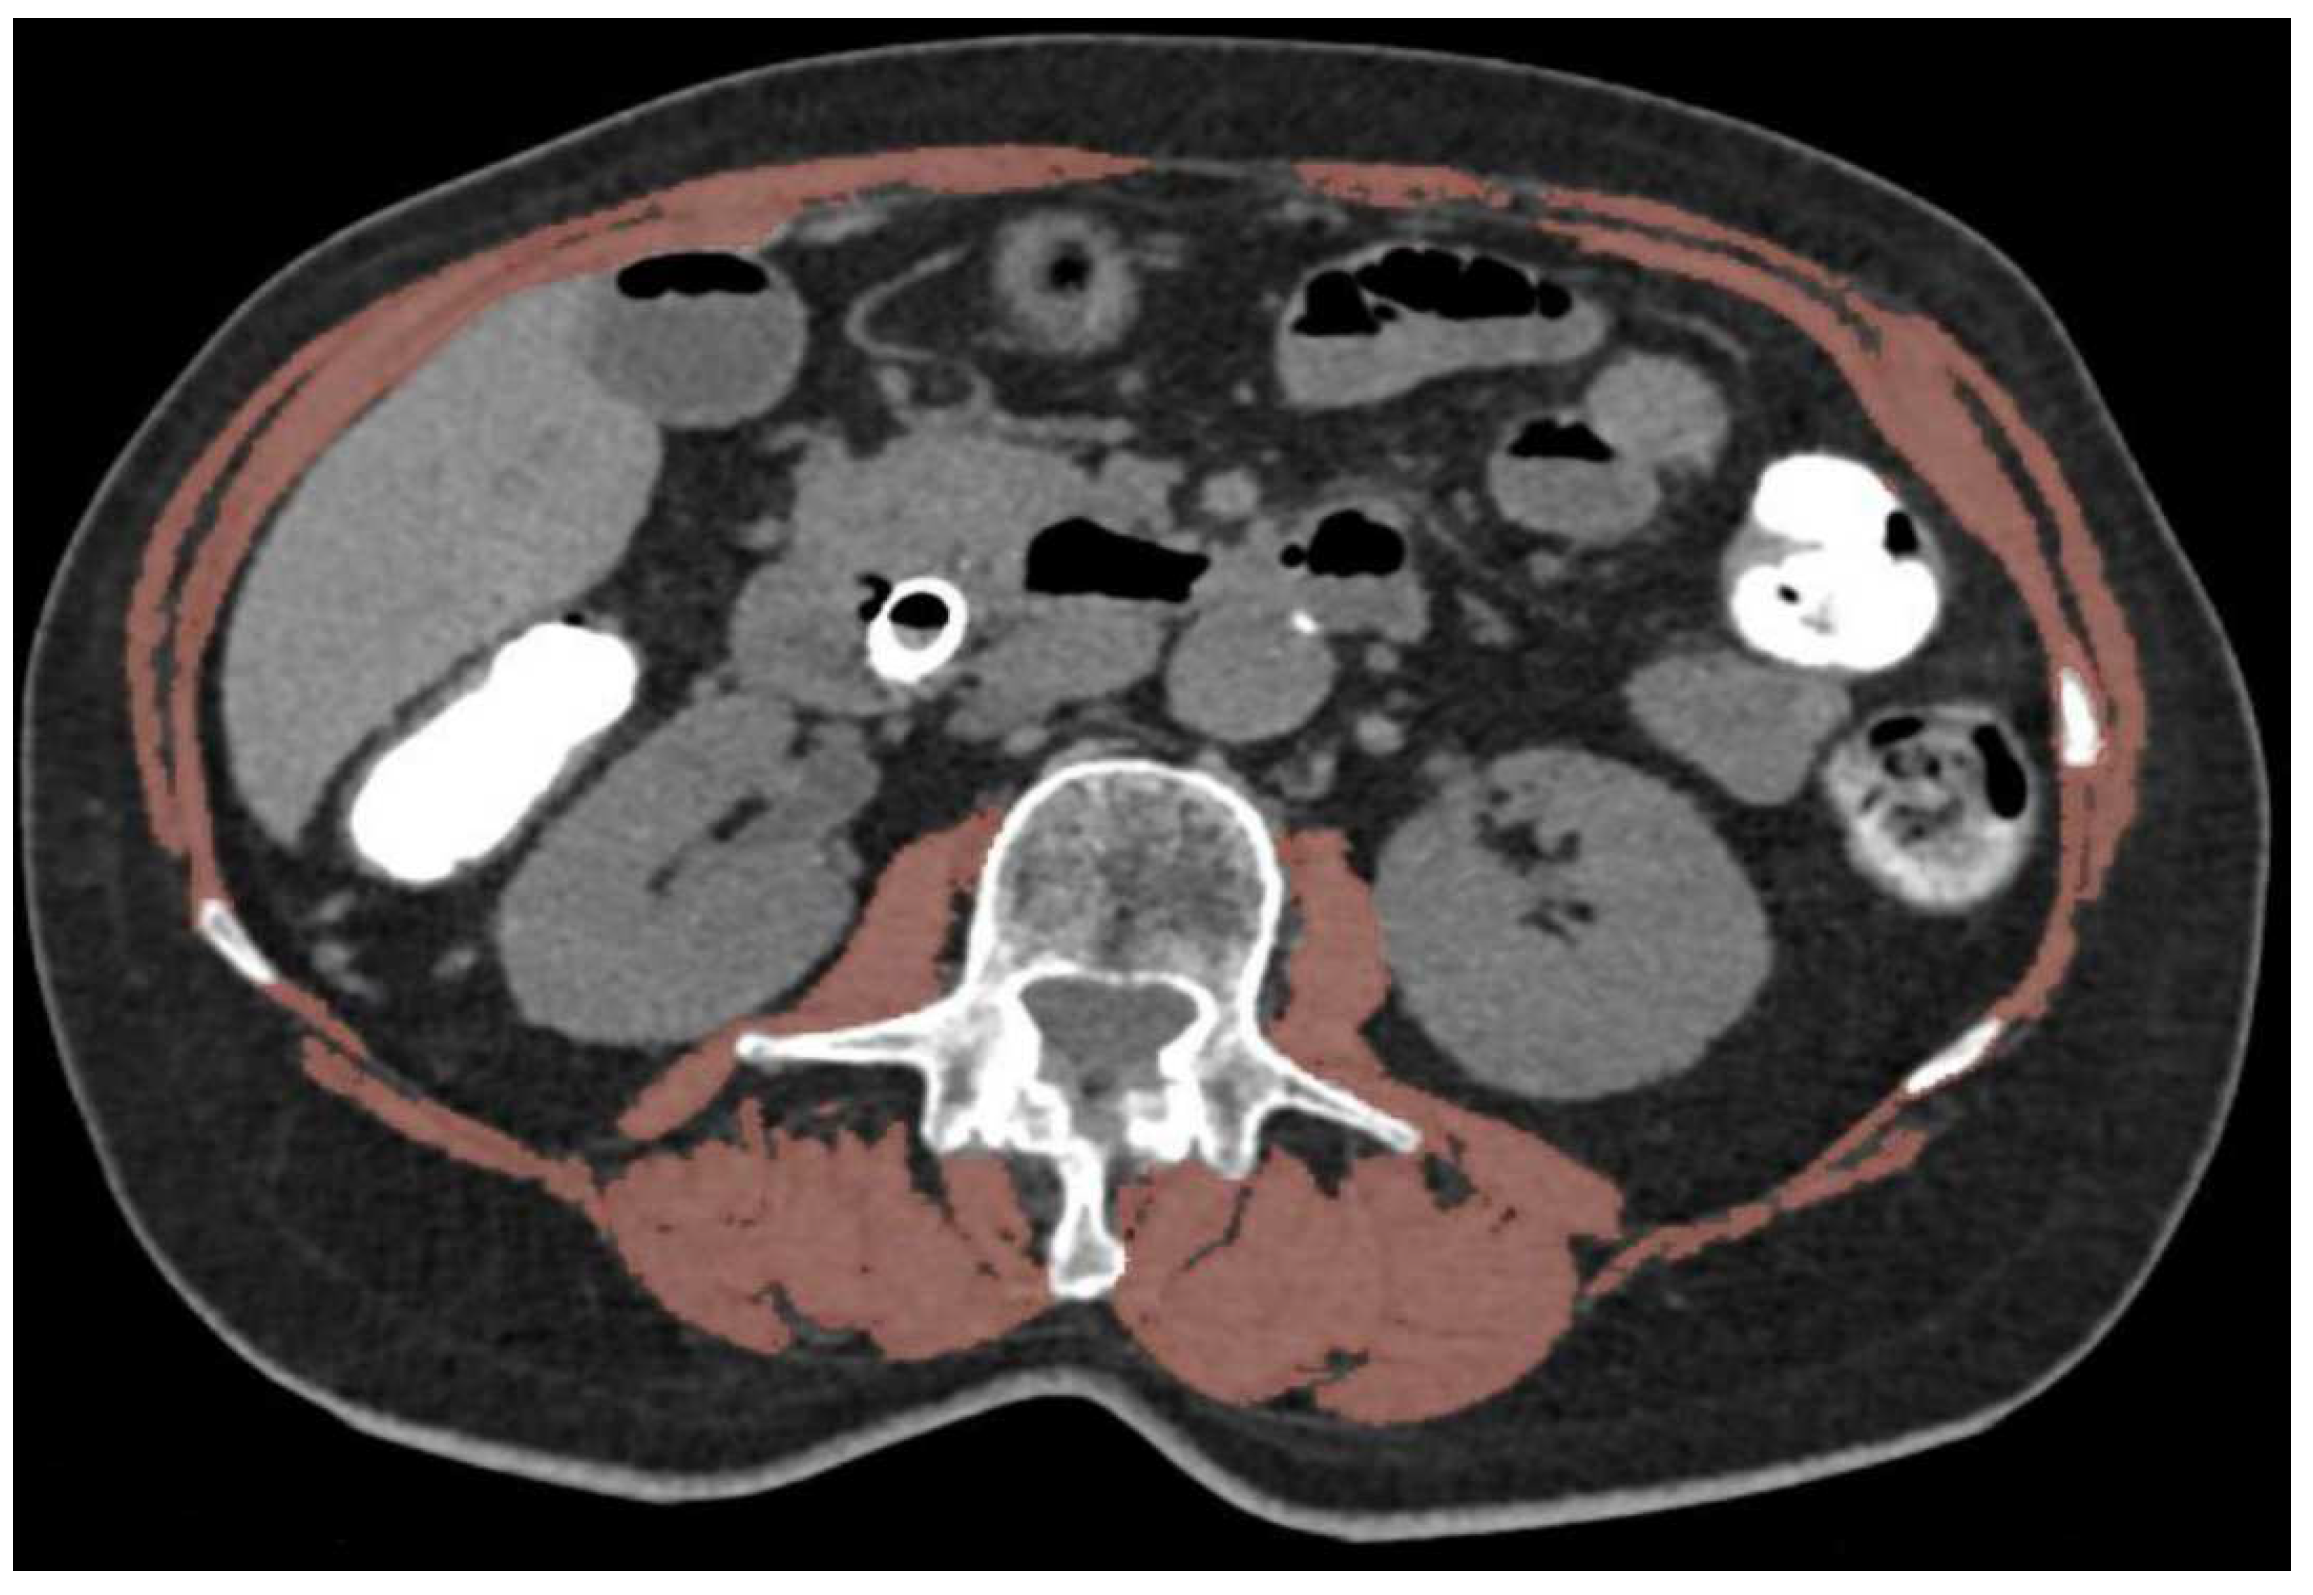

2.2. Body Composition Evaluation

- Prado, C.M. Body composition in the promising role of CT scans. Curr. Opin. Clin. Nutr. Metab. Care 2013, 16, 525–533. [Google Scholar] [CrossRef]